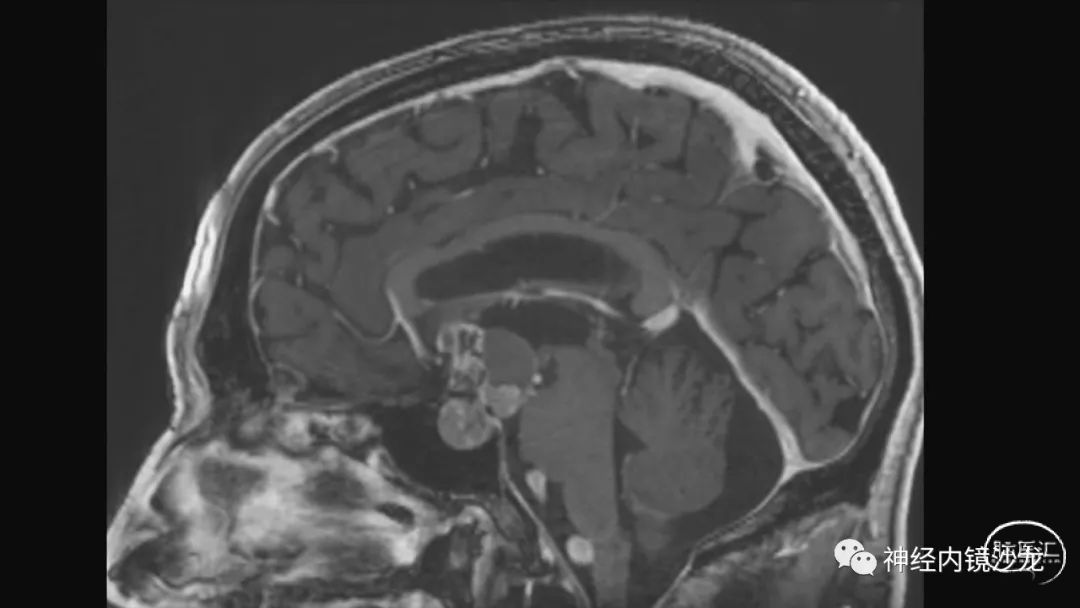

从事神经外科十余年,擅长神经外科肿瘤诊治,尤其是神经内镜微创手术治疗垂体瘤、颅咽管瘤、脑膜瘤等颅底肿瘤